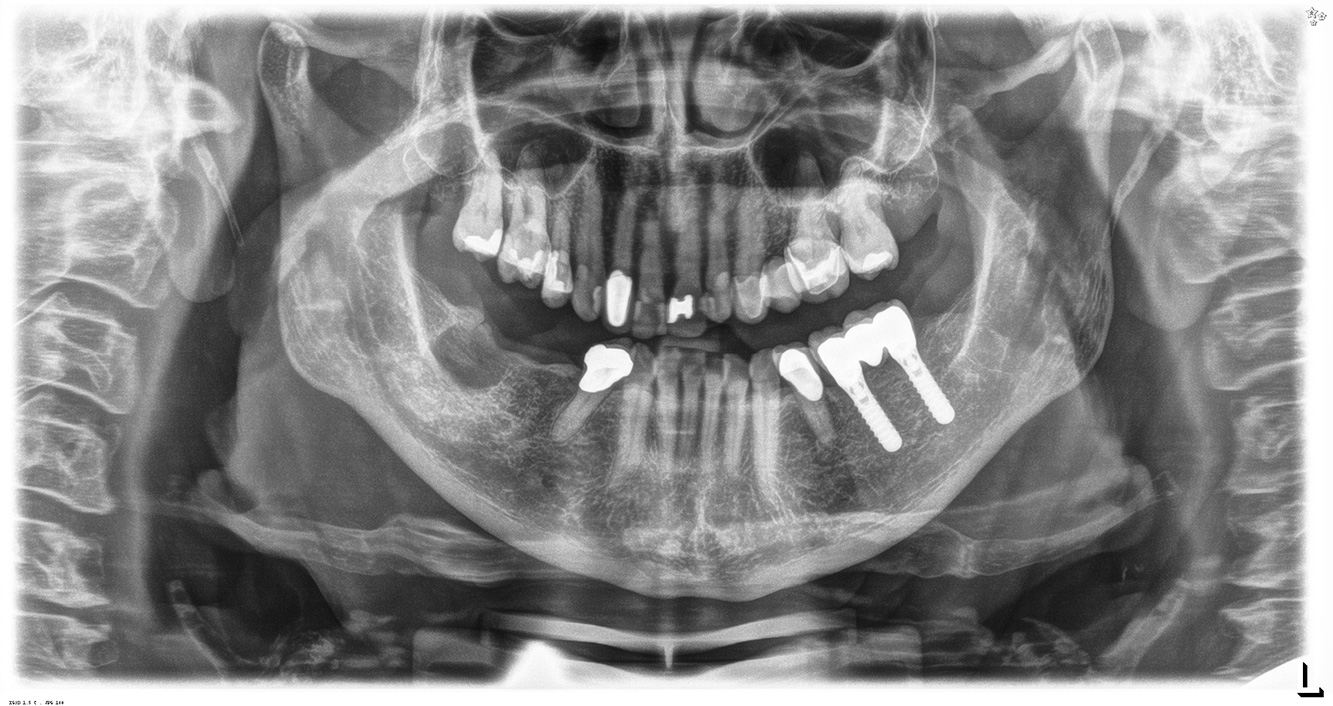

The healthy patient with pre-existing periodontal disease & peri-implantitis

A 52-year-old patient presents at a preventive care session. The patient has no systemic disease and is not taking any medication. He has had various dental treatments and also has two active carious lesions. In addition, the patient has four implants (2nd, 3rd and 4th quadrants). He is revealed to have early periodontal disease (stage IV, grade B). His periodontal condition is stable; a probing depth of Probing depths (ST) of 5 mm is only evident at the implant in region 36. Gingivitis is also identified. more

The healthy patient with early periodontal disease

The 68-year-old patient has no general health conditions and is not taking any medication that may be relevant to her oral health, and her lifestyle does not pose any particular risk. The patient has two dental implants (3rd quadrant, for five years) and a previous case of periodontal disease (stage IV, grade B periodontitis) with tooth loss. Currently the periodontal conditions are stable. However, periodontitis significantly increases the biological complications of implantations and there is a risk of implant loss (21). Four recommendations can be determined for the prophylaxis session. more